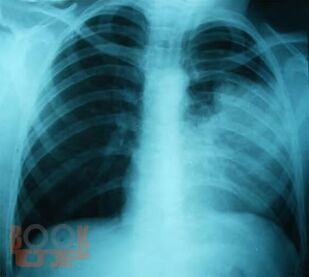

В части I представлен учебный материал по темам «Пневмония» и «Острые инфекционные деструкции легких». По каждой теме изложены современные научные данные по этиологии, патогенезе, классификации, клинике, методах диагностики, лечения и профилактики заболеваний, способствующие формированию у обучающихся общепрофессиональных компетенций ОПК-4, ОПК-5, ОПК-7 и профессиональных компетенций ПК-5, ПК-6, ПК-8, ПК-10, ПК-11. Для самоконтроля обучающимися сформированности компетенций предложены тестовые задания и ситуационные задачи с эталонами ответов, составленные авторами по учебному материалу с учетом индикаторов достижения компетенций.